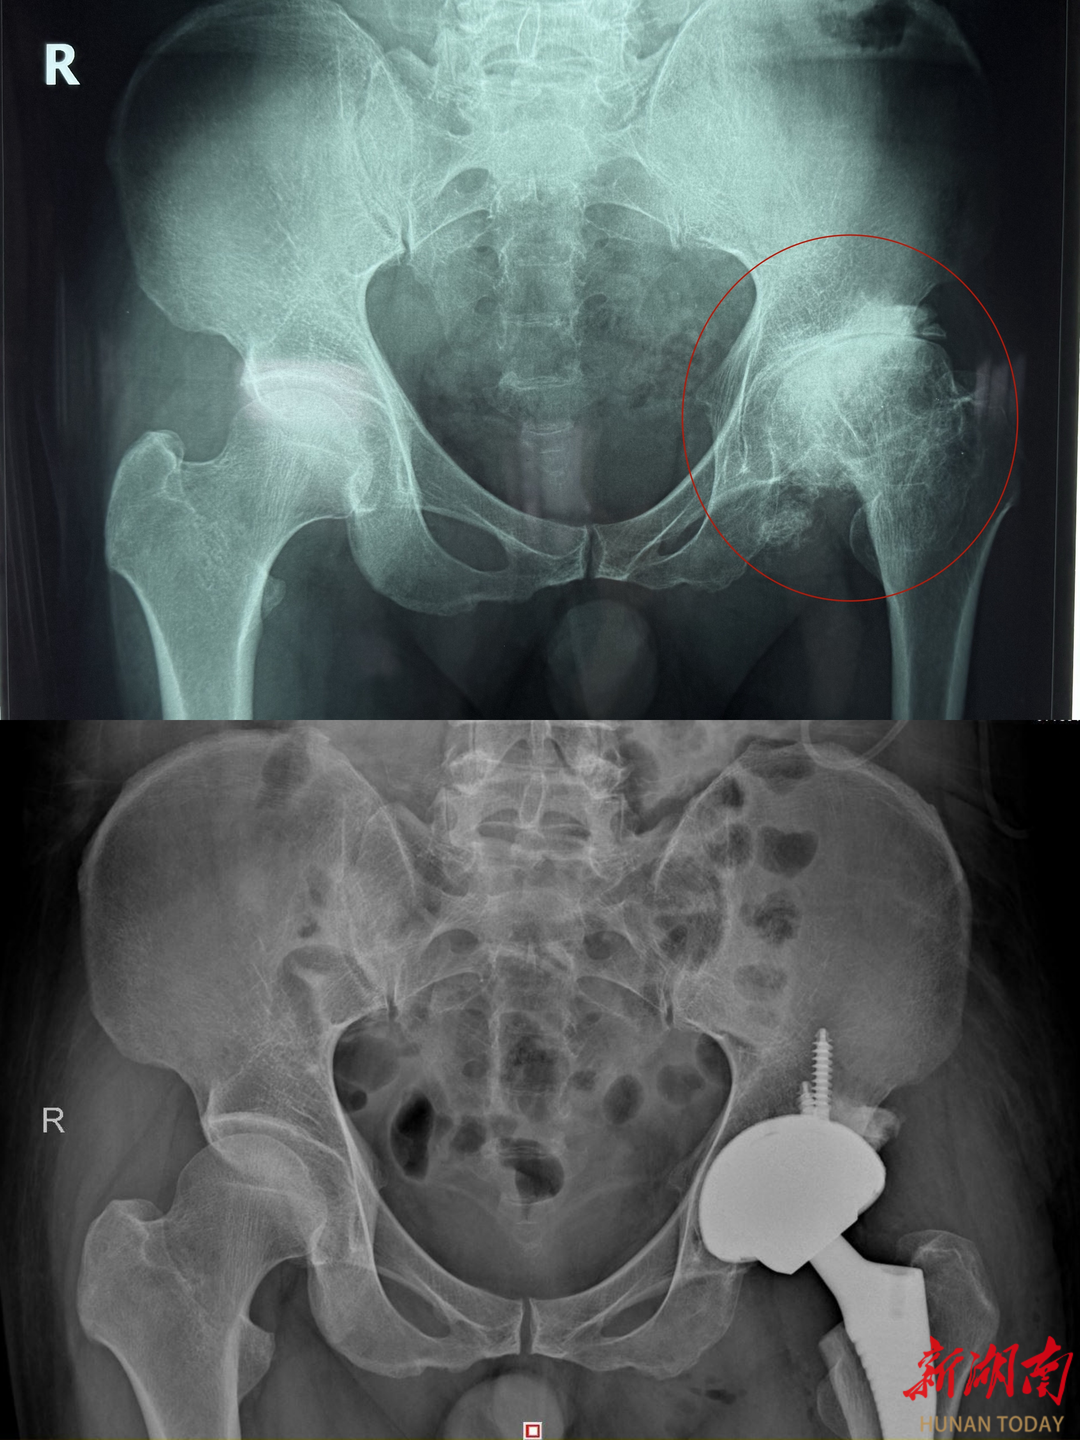

患者术前术后影像对比

第三,晚期(塌陷严重、疼痛剧烈):全髋关节置换术是目前最成熟、效果最确切的治疗方式,术后可快速恢复行走与日常活动,生活质量显著提高。